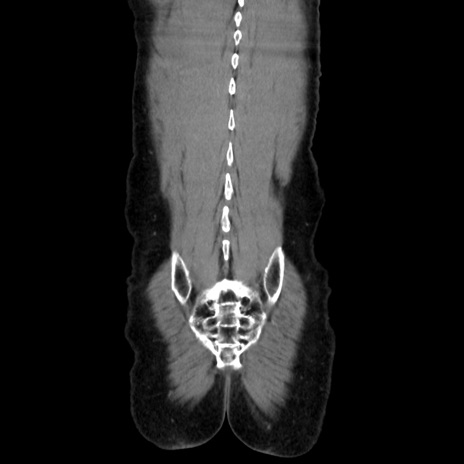

横断像